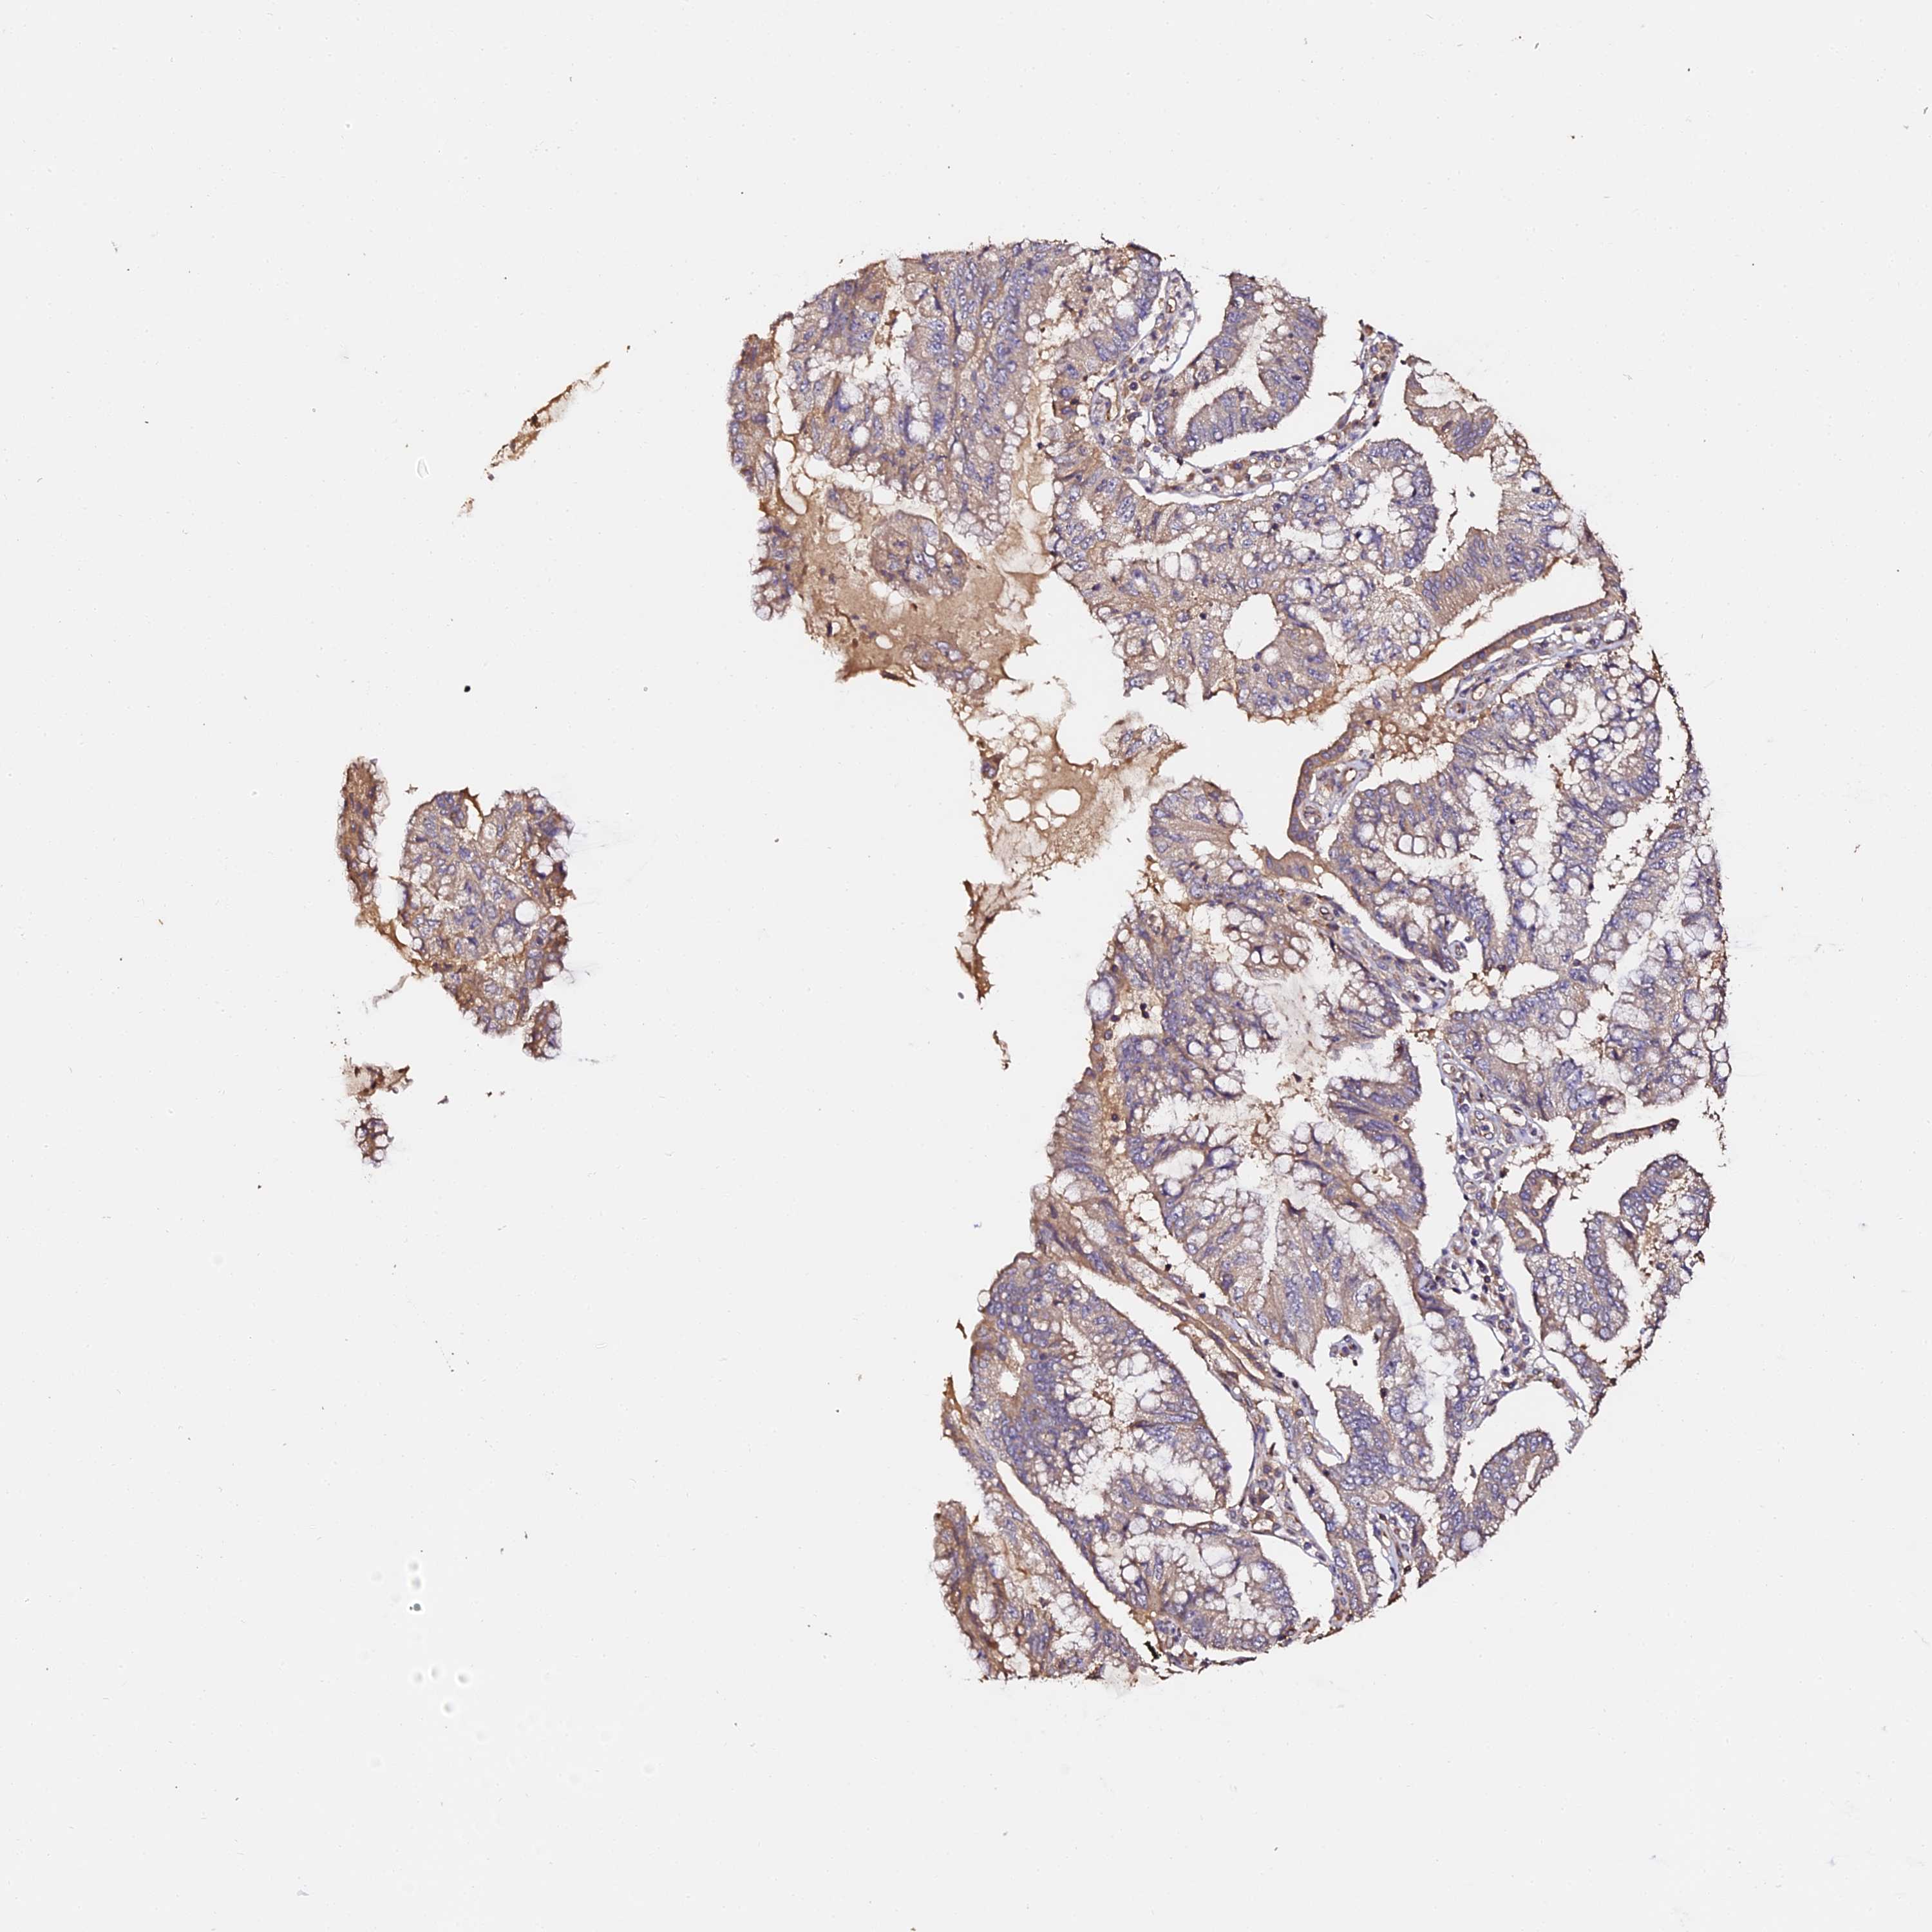

PANCREATIC CANCER - Protein expressioni

A mouse-over function shows sample information and annotation data. Click on an image to view it in a full screen mode. Samples can be filtered based on level of antibody staining by selecting one or several of the following categories: high, medium, low and not detected. The assay and annotation is described here.

Note that samples used for immunohistochemistry by the Human Protein Atlas do not correspond to samples in the TCGA dataset.

Antibody stainingi

Antibody staining in the annotated cell types in the current human tissue is reported as not detected, low, medium, or high, based on conventional immunohistochemistry profiling in selected tissues. This score is based on the combination of the staining intensity and fraction of stained cells.

Each image is clickable and will lead to virtual microscopy that enables deeper exploration of all samples and also displays staining intensity scores, fraction scores and subcellular localization as well as patient and tissue information for each sample.

Antibody HPA039611

Staining

High

Medium

Low

Not detected

Intensity

Strong

Moderate

Weak

Negative

Quantity

>75%

75%-25%

<25%

None

Location

Nuclear

Cytoplasmic/membranous

Cytoplasmic/membranous,nuclear

Adenocarcinoma, NOS